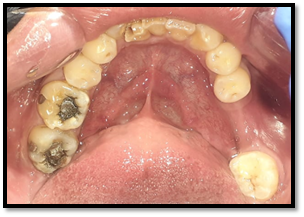

Paciente de sexo masculino de 32 años de edad, Asintomático, en la exploración clínica intraoral se observa ausencia del órgano dentario Nº 4, 2. No hay la presencia de cambios de coloración en la mucosa del sector anterior del cuerpo de la mandíbula, a la palpación no refiere dolor.

Imagen 1. Fotografías intraorales